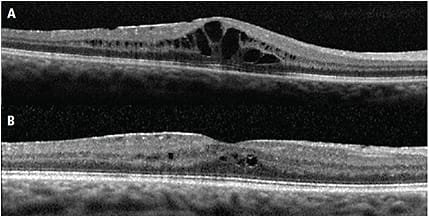

Œdème Maculaire après Chirurgie de Cataracte : l’Irvine-Gass L’œdème maculaire cystoïde postopératoire, également connu sous le nom de syndrome d’Irvine-Gass, est une complication qui peut survenir après une chirurgie de la cataracte. Bien que la chirurgie de la cataracte soit l’une des interventions les plus pratiquées et les plus sûres en ophtalmologie, cette complication mérite…